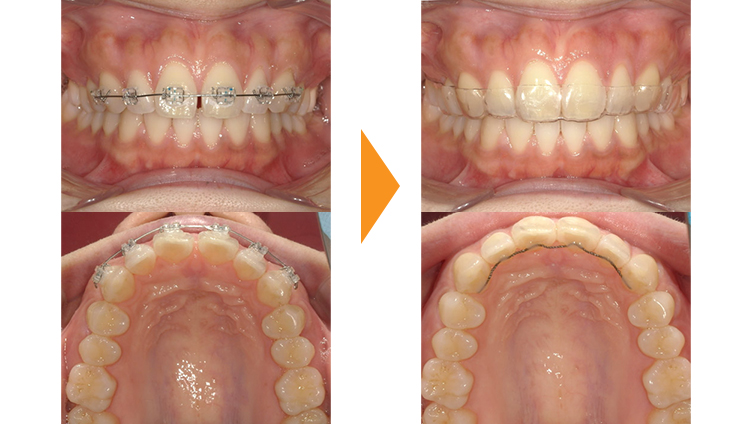

全体的な歯並びの問題やかみ合わせの問題がほとんどなかったため、ご本人の希望されていたすきっぱ(正中離開)を部分矯正で治療した症例です。

インビザラインでの治療も可能な症例ですが、コストがかかりすぎるためワイヤー矯正を選択されました。当院もこのような軽度の方は費用面での問題からワイヤー矯正をお勧めすることが多いです。

すきっぱは後戻りがしやすい歯並びなので、矯正後は歯の裏側からワイヤー固定を使用し、マウスピースも継続して使用していただいています。

ワイヤーをつける前歯の数は、前歯2本だけの場合もあれば上顎全体の14本つける場合もあります。この患者様は前歯6本に矯正器具を装着しました。

| 初診時 | 27歳女性 |

|---|---|

| 主訴 | すきっぱが気になる |

| 期間 | 約7か月 |

| 矯正 | ワイヤー矯正 |

| 費用 | 基本検査22,000円・契約料165,000円・調整料5,500円/月(税込) |

| 治療上のリスク | 歯磨き不良の場合はむし歯になる可能性。 習癖に伴う後戻りの可能性。 |